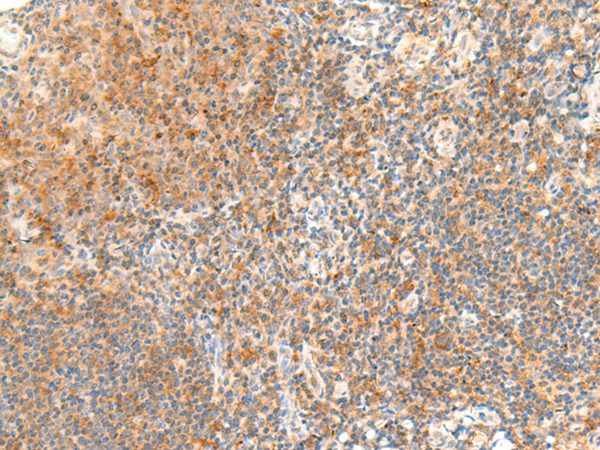

分类: 科研抗体货号: P13516别名: GPCR; bA86F4.3应用: WB,IHC反应种属: Human